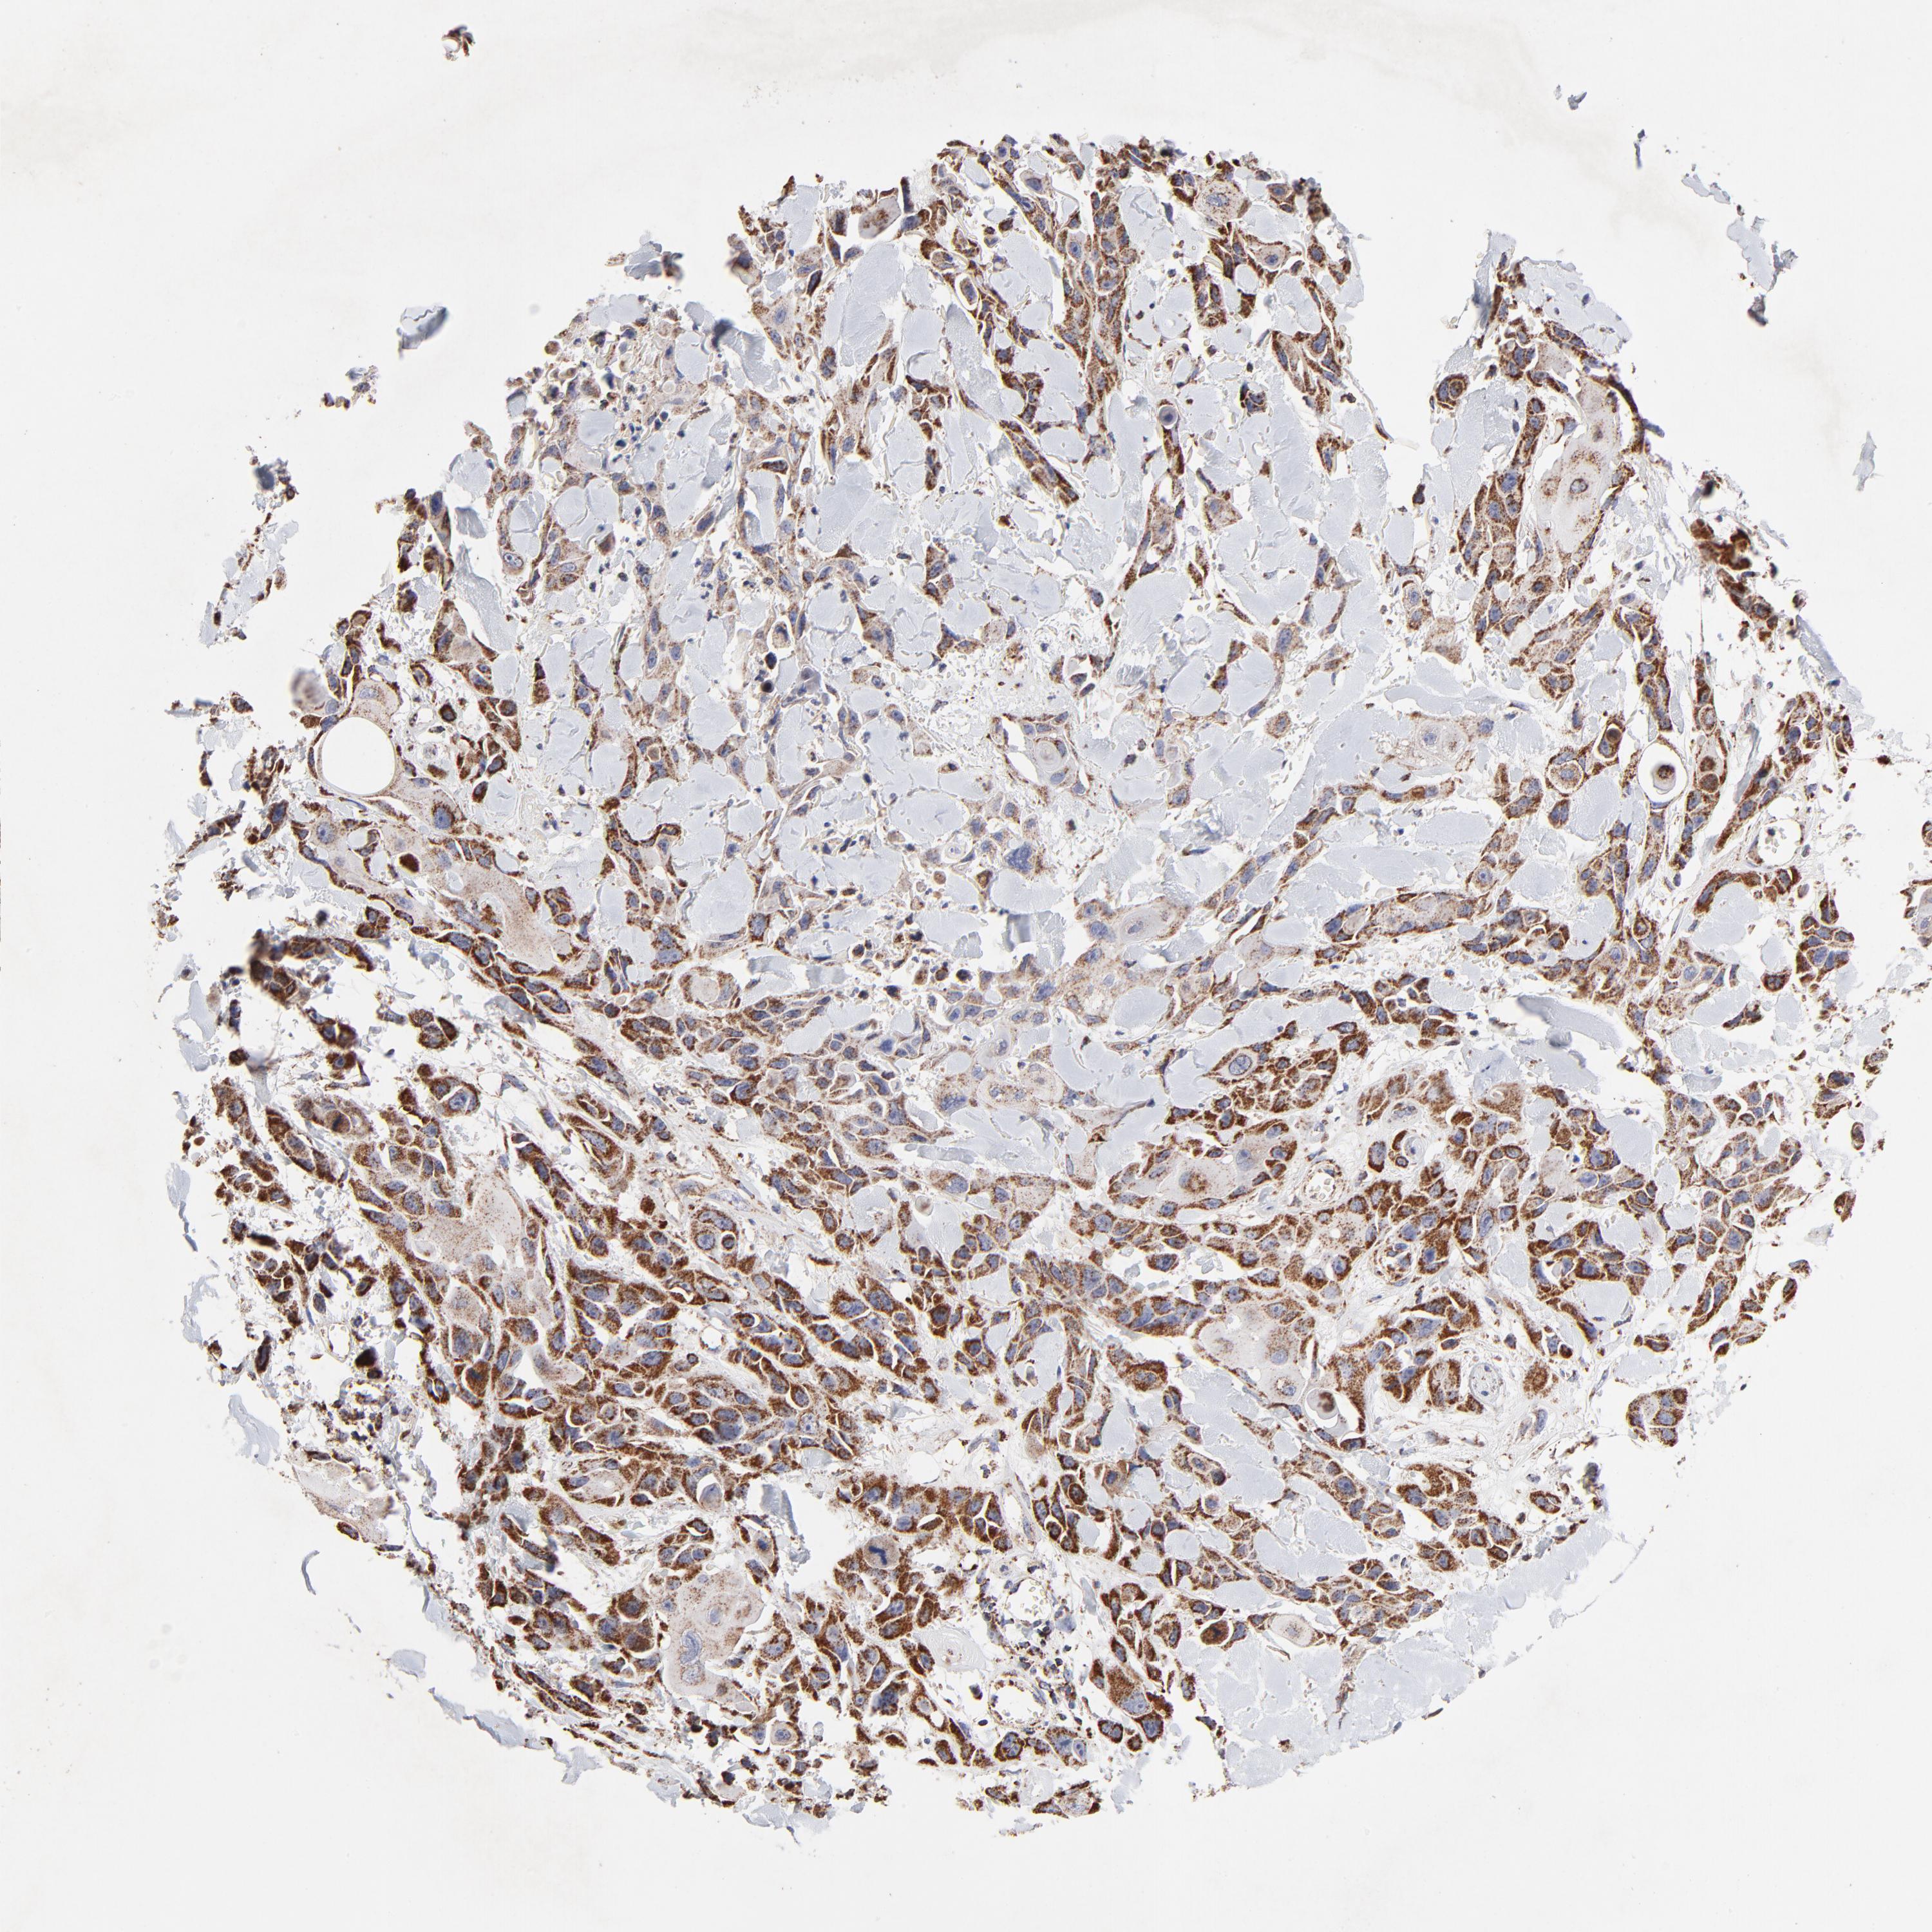

SKIN CANCER - Protein expressioni

A mouse-over function shows sample information and annotation data. Click on an image to view it in a full screen mode. Samples can be filtered based on level of antibody staining by selecting one or several of the following categories: high, medium, low and not detected. The assay and annotation is described here.

Antibody staining in the annotated cell types in the current human tissue is reported as not detected, low, medium, or high, based on conventional immunohistochemistry profiling in selected tissues. This score is based on the combination of the staining intensity and fraction of stained cells.

Each image is clickable and will lead to virtual microscopy that enables deeper exploration of all samples and also displays staining intensity scores, fraction scores and subcellular localization as well as patient and tissue information for each sample.

Antibody HPA002866

Staining

High

Medium

Low

Not detected

Intensity

Strong

Moderate

Weak

Negative

Quantity

>75%

75%-25%

<25%

None

Location

Nuclear

Cytoplasmic/membranous

Cytoplasmic/membranous,nuclear

Squamous cell carcinoma, NOS

Basal cell carcinoma